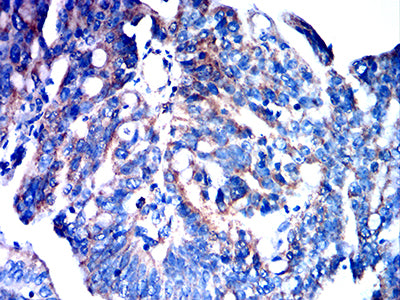

- Immunohistochemical analysis of paraffin-embedded human cervical cancer tissues using FPR3 mouse mAb with DAB staining.

- Immunohistochemical analysis of paraffin-embedded human rectum cancer tissues using FPR3 mouse mAb with DAB staining.